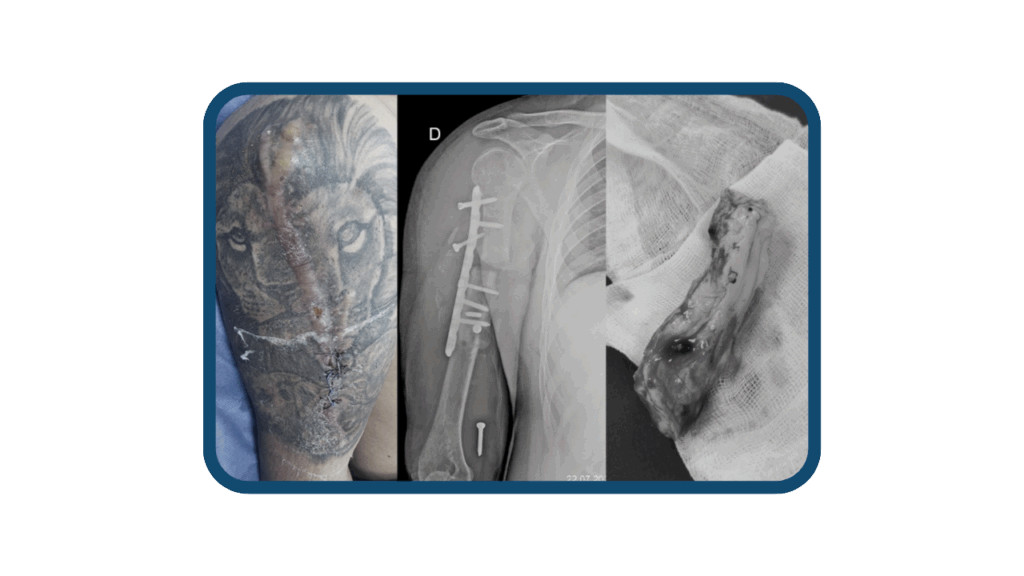

La osteomielitis es una de las infecciones más comunes que suelen llegar a Clínica Arthrosalud. Es una condición que puede causar dolor, inflamación y daño óseo. Por lo que requiere de intervención especializada por parte de nuestros traumatólogos, con el fin de eliminar la infección y preservar la función del hueso con una reconstrucción ósea.